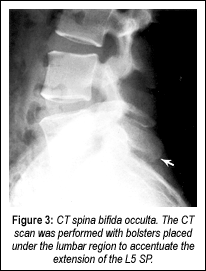

I will demonstrate one case where this was a definite factor in a patient's lower back pain. A 28-year-old male developed lower back pain at the age of 19 while lifting heavy boxes. He had intermittent recurrences of lower back pain since the initial episode. He described the pain as "pins and needles" in the base of his back. The pain radiated to the left hip, with associated intermittent numbness in the left calf. Symptoms were aggravated by standing and physical activity, and were relieved by lying down. He had no pain at night, but did complain of morning stiffness. Neurological examination revealed absent Babinski signs bilaterally, and diffuse, mild tenderness over the lower lumbar spinous processes and paraspinal muscles. Anterior-posterior (Figure 1) and lateral views (Figure 2) demonstrated spina bifida occulta at the S1 segment associated with an elongated L5 SP. Computerized tomography (CT) revealed spina bifida occulta, the classic clasp-knife deformity, with encroachment upon the spinal canal (Figure 3).